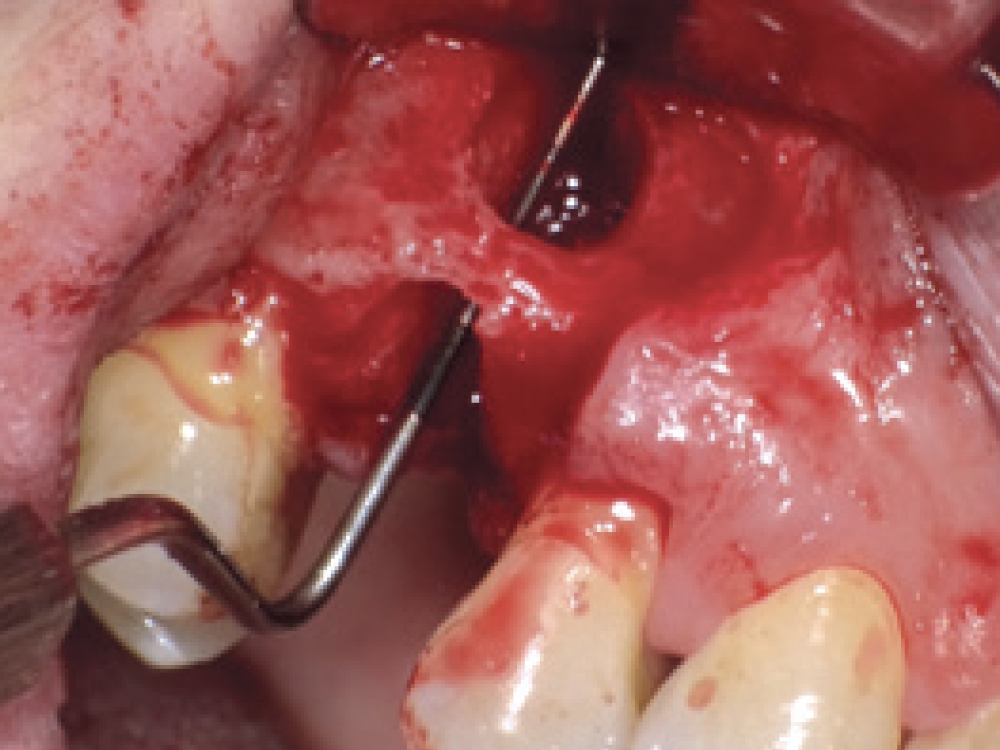

CBCT Scan fenestration

Premolar extraction of fenestration

Preoperative cross-sectional CBCT scan confirming fenestration at the site of a premolar requiring extraction, and buccal view of the exposed defect following flap reflection.